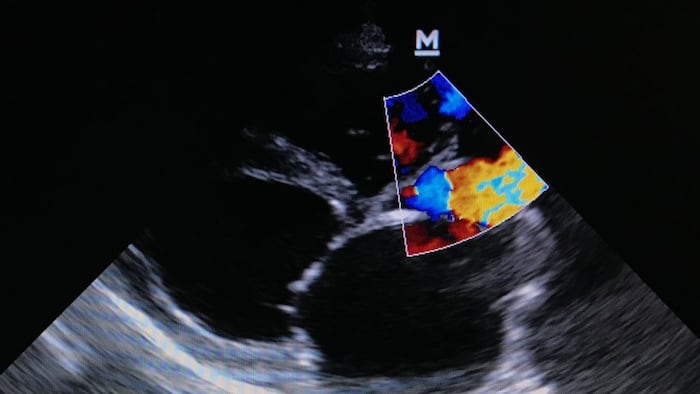

TRiCares announced first implantation of the Topaz transfemoral tricuspid heart valve replacement system as part of the company’s EU pivotal study. If all goes to plan, the device will compete with Edwards’ Evoque system. The announcement follows the company’s $50m series D funding raise in July.